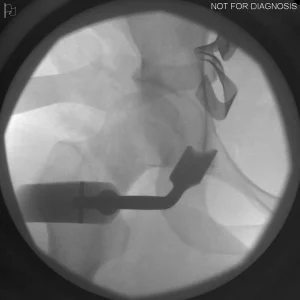

During a PAO, the surgeon carefully cuts the bone around the hip socket and repositions it to provide better coverage of the femoral head. The socket is then fixed in its new position using screws. The goal is to improve hip stability, reduce pain, and preserve the patient’s natural hip joint.

Diagram 3: Hip After Periacetabular Osteotomy (PAO)

• Acetabulum repositioned to improve femoral head coverage

• Load more evenly distributed across the joint

• Screws shown securing the acetabulum in its new position